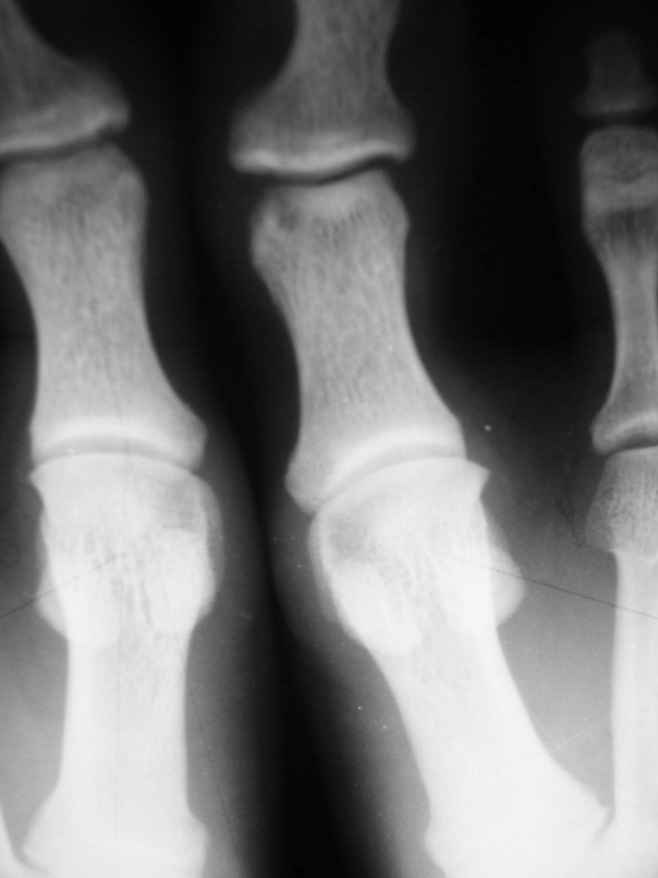

2-Пациент С.,32 лет,аневризмальная костная киста левой большеберцовой кости (Рис. 3,4), проходит лечение.

Rggrammi 32 letnego bolnogo skoree pohozhi na Gigantokletochnuy opuhol.

На представленных снимках рентгенологическая картина АКК не соответствует - в первом случае рентгенологическая картина (учитывая центральное расположение ) более соответствует солитарной костной кисте м.берц. кости, а в фаланге - кистовидная перестройка, во втором случае - гигантоклеточная опухоль